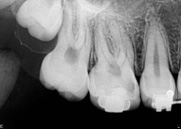

antes depois